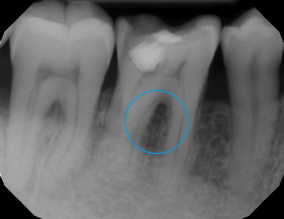

Ozone Treatment :

Reverse Gum Disease: Bone Healing

Reverse Tooth Decay: After 10 sessions of ozone gas infiltration treatment, the tooth regains its shape.